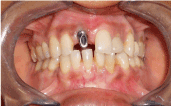

A thirty five years old female patient reported with a chief complaint of missing anterior teeth and need for aesthetic restoration of the same with fixed prosthesis. She was wearing maxillary anterior removable partial denture from last 10 months. The patient gave the history of extraction due to mobility of upper anterior teeth one year back. Her medical history was non-contributory. Her expectations were reasonable and her psychological profile was good. On trans-gingival probing the presence of Seibert class II ridge in relation to maxillary anterior 11 was evident. There was a slight buccal defect in the gingiva in the region of tooth #11 due to normal shrinkage, probably exacerbated by pressure exerted from the removable appliance (Figure 1). The periapical radiograph revealed adequate bone height and mesio-distal bone width. It was explained to the patient that although implants represented an ideal treatment option, it would be necessary to simultaneously augment the bone to allow for optimal bone integration and stability of the implants. The patient agreed to the proposed surgical and prosthetic treatment plan.

Figure 1. Intra oral view showing buccal defect in #11 region.